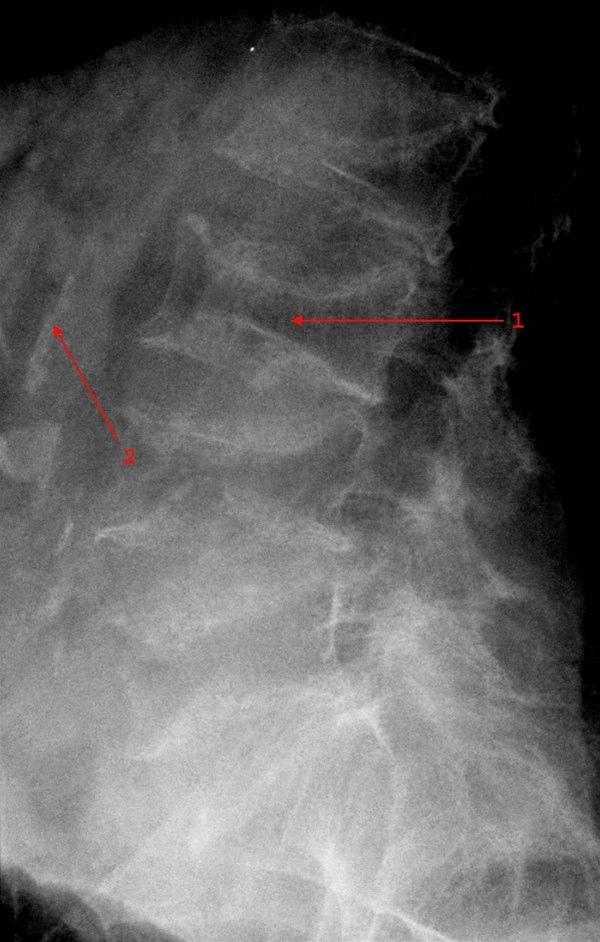

Osteoporose lumbalcolumna

Betydelig redusert kalktetthet og kompresjoner i alle lumbale virvler.

Bifunn: Veggforkalkninger i aorta

- Sammenfalt L3

- Kalk i aortaveggen